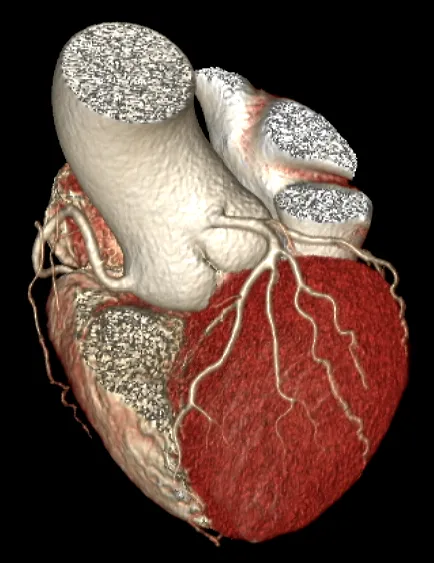

冠脉CTA:右冠动脉近段管壁软斑,管腔约轻度狭窄。左右冠状动脉起源及走行未见异常,整体呈右冠优势型。右冠状动脉(A)近段管壁则软斑影,管腔约轻度狭窄。左冠状动脉主干管壁未则明显异常,管腔未见狭窄。前降支(LAD)、第一对角支(D1)、第二对角支(D2)、左旋支(LCX)、第一钝缘支(OM1)、中间支(RI)、后降支(PDA)及后外侧支(PLB)未见确切斑块及狭窄征象。